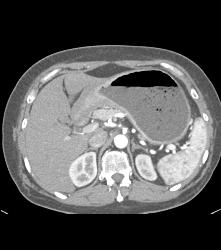

Antral Carcinoma